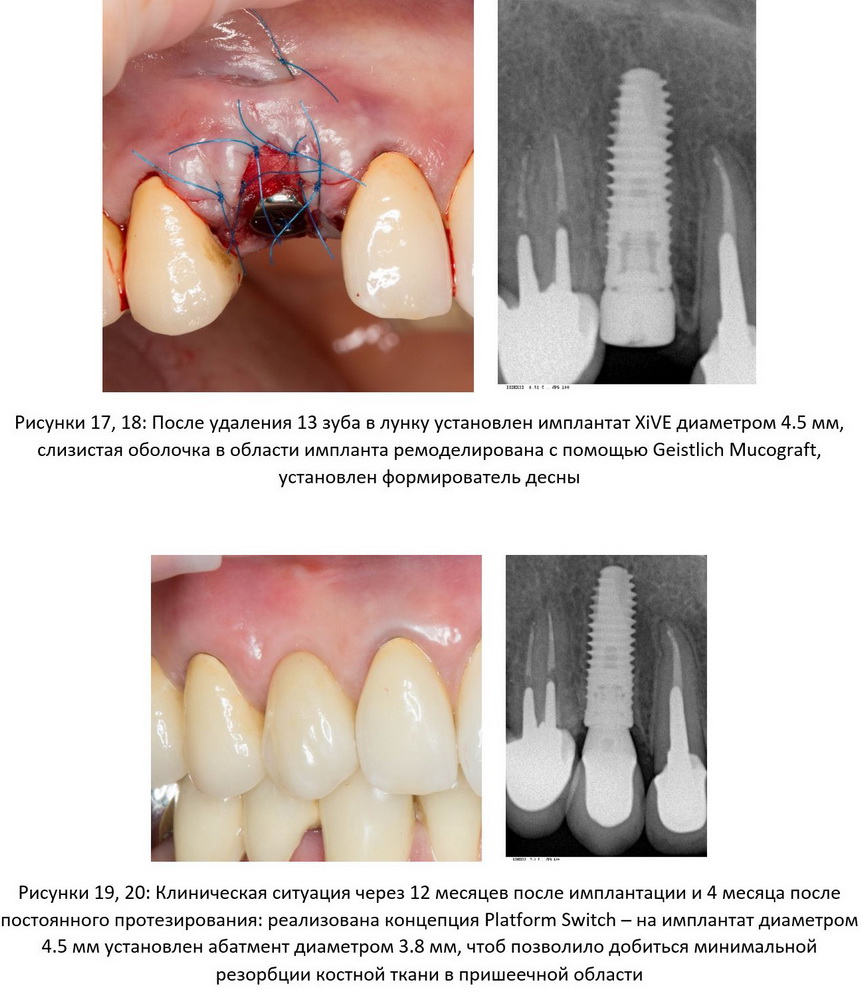

— изоляция является важным фактором выживаемости имплантов в долгосрочной перспективе. В отличие от естественных зубов, окружающая импланты слизистая оболочка не срастается ни с абатментом, ни с имплантом, образуя вокруг них что-то вроде плотной муфты, которая, однако, не препятствует проникновению микрофлоры к окружающей имплант костной ткани. Учитывая этот фактор, чем дальше точка контакта «имплант-абатмент» от точки «имплантат-костная ткань», тем меньше риски инфицирования пришеечной области импланта и развития периимплантита. Именно эту цель преследует концепция Platform Switch, переключения ортопедических платформ (рис 17, 18, 19, 20, 21, 22):